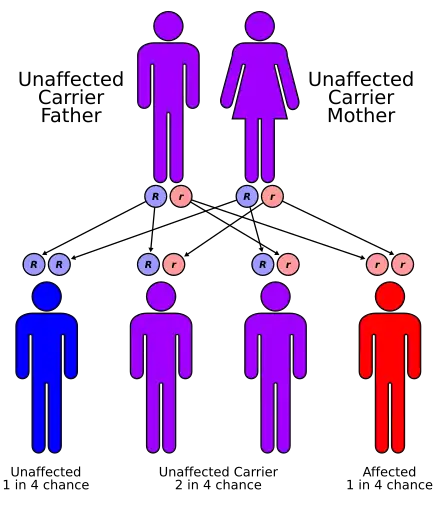

| Arterial tortuosity syndrome has an autosomal recessive pattern of inheritance | |

Arterial tortuosity syndrome exhibits autosomal recessive inheritance, and the responsible gene is located at chromosome 20q13.[6][2] The gene associated with arterial tortuosity syndrome is SLC2A10 and has no less than 23 mutations in those individuals found to have the aforementioned condition.[2][3]